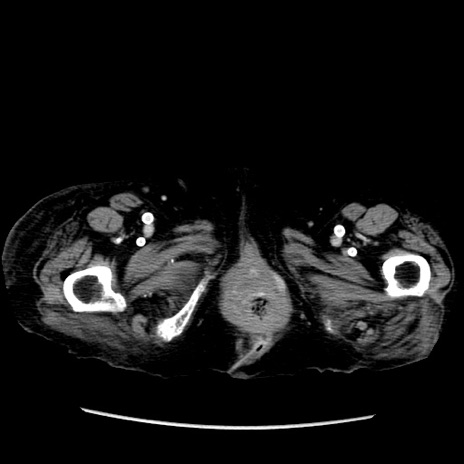

症例14(横断像)

【症例】 90歳代女性

【主訴】 腹痛・嘔吐

【現病歴】今朝から左側腹部痛を認めた。 経過観察していたが、嘔吐を認めたため来院。

【既往歴】 子宮癌術後

【身体所見】 意識清明、BP 127/54mmHg、P 98bpm Sp02 95%(RA)、BT 35.8°C、腹部平坦・軟腸ぜん動音聴取良好、右下腹部圧痛(+) 反跳痛なし

【データ】WBC 9800、CRP 0.46